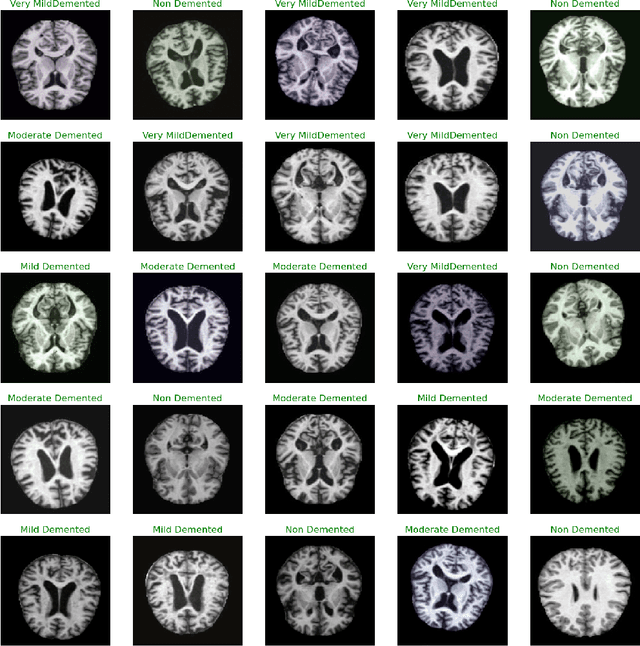

Abstract:Exploring the application of deep learning technologies in the field of medical diagnostics, Magnetic Resonance Imaging (MRI) provides a unique perspective for observing and diagnosing complex neurodegenerative diseases such as Alzheimer Disease (AD). With advancements in deep learning, particularly in Convolutional Neural Networks (CNNs) and the Xception network architecture, we are now able to analyze and classify vast amounts of MRI data with unprecedented accuracy. The progress of this technology not only enhances our understanding of brain structural changes but also opens up new avenues for monitoring disease progression through non-invasive means and potentially allows for precise diagnosis in the early stages of the disease. This study aims to classify MRI images using deep learning models to identify different stages of Alzheimer Disease through a series of innovative data processing and model construction steps. Our experimental results show that the deep learning framework based on the Xception model achieved a 99.6% accuracy rate in the multi-class MRI image classification task, demonstrating its potential application value in assistive diagnosis. Future research will focus on expanding the dataset, improving model interpretability, and clinical validation to further promote the application of deep learning technology in the medical field, with the hope of bringing earlier diagnosis and more personalized treatment plans to Alzheimer Disease patients.